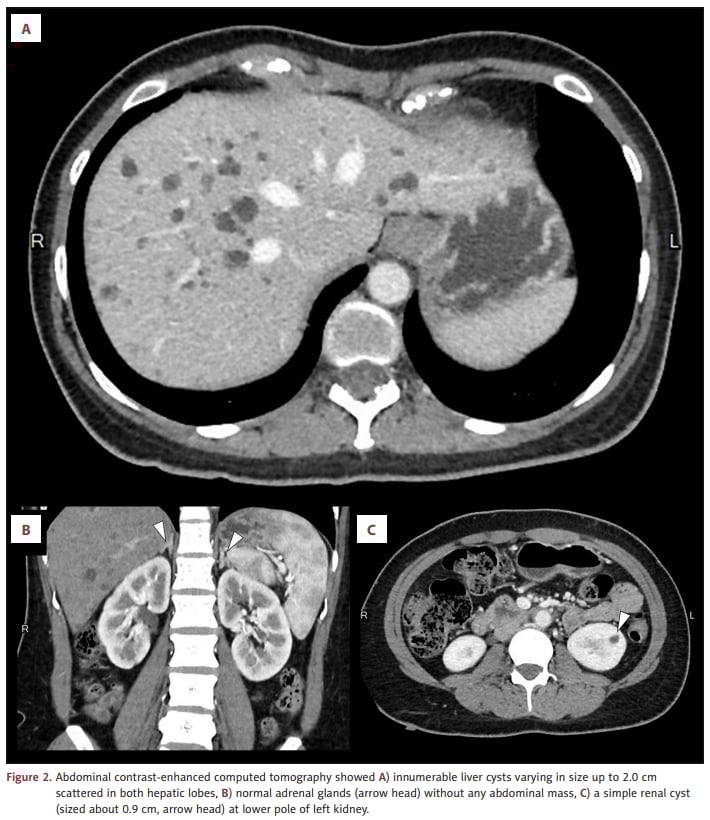

本病例腹部增强CT显示:肝脏散在分布大量囊肿(最大约2.0 cm),同时仅见左肾下极一个约0.9 cm的单纯性肾囊肿,肾上腺正常、未见腹部肿块。

腹部增强CT提示大量肝囊肿,同时肾上腺正常、仅见单纯性肾囊肿

由于“多囊肝不是NF1典型表现”,团队进一步进行WES并覆盖多囊肝相关候选基因(包括PKHD1、PKD1、PKD2等)。